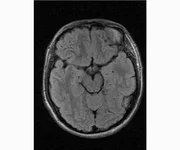

делал в обласной на siemense.В заключении выданом мне через 15мин.после мрт (легкая дегидрация)

Меня смутил факт выдачи заключения через 10мин(наверно они у них зарание напечатаные)я не медик.достаточно мимолётного взгляда на снимки?А вы видете на них гидроцефалию? Я лиш спросил куда идти с результатами томографии?и не хотел никого роздражать.

Я попросил взглянуть на снимки и сказать видна.ли на них гидроцефалия?или куда обратится за консультацией по этому вопросу?В мрт снимках наверно розбирается любой нервопатолог(я так предположил)

Я уже говорил, что независимо от того, есть на МРТ гидроцефалия или нет, лечиться тебе нужно только в том случае, если есть какие-либо проявления болезни, иначе на все эти анализы можешь забить... Но давай все-таки разберемся с томограммой.

Итак, с самого начала томограмма обозначала срез какого-либо органа на определенной глубине, позволяла заглянуть вовнутрь. При компьютерной томографии аппарат делает десятки срезов головного мозга в разных направлениях и из этого множества срезов он моделирует полноценное объемное изображение мозга в натуральную величину. Обрати внимание, компьютер работает не с этими миниатюрными изображениями, а с трехмерной моделью в масштабе 1:1. Эту модель вдоль и поперек анализирует суперсовременный компьютер, выполняющий миллионы операций в секунду. Только ***** может пытаться перепроверить компьютер, ведь человеку не хватит всей жизни чтобы проанализировать то, что компьютер с тобой сделал за 10 минут. Я хочу, чтобы ты это понял!

Ты разместл здесь несколько миниатюр и хочешь, чтобы врач по ним создал полноценное объемное изображение в натуральную величину, а потом осмотрел его со всех сторон и дал заключение? Но ведь это невозможно. Это просто насмешка над врачом, это издевательство над здравым смыслом. Принеси Букеру уменьшенный в 50 раз снимок зуба и спроси у него, в каком состоянии там корневые каналы. Или давай я дам тебе скрин со спутниковой карты города и попрошу тебя описать, какого цвета и какой модели запечатленная со спутника машина, какой у нее гос.номер, сколько в ней пассажиров, сколько из них мужчин и сколько женщин...

Надеюсь, ты понимаешь, что это невозможно. И воссоздать по приведенным тобой аватарам полную картину мозга тоже невозможно. Пойми, если уж называть вещи своими именами, то ты запостил полнейшую ***ню! Ты не хотел никого обидеть, ты ведь сам не ведал, что творил. Ты продемонстрировал полнейшую медицинскую безграмотность и полное невежество, но претензий к тебе нет. Ты ведь не один такой. Ты пожелал того, что сделать невозможно, и тут же у тебя нашлась сочувствующая, некая П., которую, по большому счету, надо бы послать в П., коль уж она считает, что врач должен тут сделать немедленно и бесплатно то, что делает немецкий компьютерный томограф ценой в миллионы долларов.